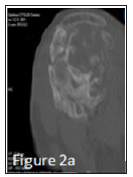

A 30 years old patient with no antecedent had a painful posterior dislocation of the right shoulder, due to an initial epileptic seizure (Figure 1a). Neurological examination and cerebral Computed tomography (CT) showed no abnormality; he was treated by an anti-epileptic (Valproic Acid). The reduction of the posterior dislocation with sedation caused a fracture of the head without neurological injury (Figure 1b). The patient was operated on three occasions: he was operated on day one for the initial fracture (anterior approach, Figure 1c). The postoperative was marked on day seven by a superficial cutaneous infection (C-reactive protein at 54 mg / L, normal complete blood count, and preservation of the general state). The sampling showed an enterobacter clouaca complex. He was treated by antibiotherapy based on gentamicin 160mg / L for five days and ciprofloxacin for two months, the evolution was remarkable after one month. He was operated at day 7 for insufficient reduction of the humeral head (removal of material and introduction of new material (Figure 1d, anterior and posterior approach). There was no sign of deep infection. The progress was marked by the absence of recurrence of epilepsy since the first crisis and stiffness. At day 30 of dislocation, there was an appearance of periarticular ossification compromising the function of the shoulder (Figures 1e & 1f). Computed tomography (CT) of the shoulder showed the localization of ossification (Figures 2a-2c). At day 45, Rehabilitation sessions were done but without improvement. He was operated at day 60 of the last act for the removal of the material without sign of infection (anterior approach). Currently, the patient always keeps stiffness on the activities of the daily life, the hand-mouth is possible but the limitation of the abduction and the external rotation makes difficult hand-neck. Scintigraphic evaluation of osteoblastic activity would be realized to decide on a possible arthrolysis of the shoulder.

Figure 2A: Heterotopic ossification on a sagittal cross section in computed tomography (CT) of the shoulder.